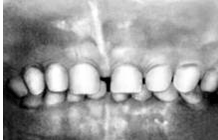

Рис 12. Молочные боковые резцы, адентия, 2 I 2 В связи с этим обстоятельством, а также потому, что они расположены на большем удалении от сагиттальной плоскости, лечение третьих моляров по поводу пульпита и периодонтита всегда вызывает значительные трудности. Дополнительный второй корень нередко бывает у второго премоляра верхней челюсти, реже у клыков и резцов. Даже при наличии одного корня не исключается образование дополнительных каналов, что может быть установлено при рентгенографии в процессе эндодонтического вмешательства. Изменение цвета временных зубов (желтый, серо-желтый, темно-коричневый, желто-зеленый, коричнево-зеленый, черно-коричневый, серый, зеленый, голубой, лиловый, черный) наблюдается у детей, перенесших гемолитическую болезнь новорожденных. Образующийся при гемолизе эритроцитов непрямой билирубин, откладываясь в тканях зуба, приводит к окрашиванию зубов в различные цвета и может влиять на процесс гистогенеза, приводя к недоразвитию эмали — системной гипоплазии. В отличие от системной гипоплазии, вызванной другими заболеваниями, гипоплазия после гемолитической желтухи, вызванной несовместимостью крови матери и ребенка по резус-фактору, обязательно сочетается с изменением окраски коронок молочных зубов. Такие зубы следует дифференцировать от «тетрациклиновых» зубов, дисплазии Капдепона. Уточнению причины изменения окраски зубов способствуют анамнез, осмотр зубов под ультрафиолетовыми лучами и гистохимически тесты на желчные пигменты. «Тетрациклиновые» зубы. «Тетрациклиновыми» называют зубы с измененной окраской, что вызвано отложение тетрациклина в тканях зуба. Он откладывается в эмали и дентине развивающихся зубов, а также в костях плода при введении в организм беременной женщины или ребенка тетрациклина при лечении различных заболеваний. Тетрациклин может вызвать не только окрашивании зубов, но и гипоплазию эмали. При введении в организм даже небольших доз тетрациклина формирующиеся в этот период зубы окрашиваются в желтый цвет. Интенсивность окраски от светло-желто до темно-желтой, что зависит от вида тетрациклина и его количества. Более интенсивная окраска наблюдается при приеме диметилхлортетрациклина, менее интенсивная —при употреблении окситетрациклина. Локализация окрашенных участков зуба связана с периодом одонтогенеза во время приема тетрациклина. Лечение беременной тетрациклином приводит к изменению окраски у ребенка передних зубов, а именно трети коронок резцов, начиная от режущего края и жевательной поверхности моляров. Полагают, что тетрациклин проникает через плацентарный барьер. Введение тетрациклина ребенку в первые месяцы жизни также приводит к окрашиванию коронок временных зубов — пришеечной части резцов и бугров у моляров и клыков. Применение тетрациклина, начиная с 6-месячного возраста ребенка, вызывает окрашивание не только временных моляров, но и постоянных зубов, формирующихся в эти сроки. Окрашивается, как правило, не вся коронка зуба, а только та ее часть, которая формируется в этот период. Зубы, окрашенные тетрациклином в желтоватый цвет, обладают способностью флюоресцировать под влиянием ультрафиолетовых лучей. Это свойство можно использовать для дифференциации от окраски зубов, вызванной другими причинами, например билирубином при гемолитической болезни новорожденного. Со временем окраска зубов под влиянием света изменяется: из желтой превращаются в серую, грязно-желтую или буровато-коричневую. Изменение окраски наблюдается преимущественно на вестибулярной поверхности передних зубов. На язычной поверхности этих зубов и на всех поверхностях коронок моляров окраска остается прежней С ослаблением окраски коронки зуба утрачивается способность ее к флюоресценции. В связи с тем, что окрашивание эмали зуба тетрациклином стойкое и в дальнейшем ткани зуба невозможно отбелить тетрациклин детям следует назначать только по жизненным показаниям и в том случае, если невозможно заменить его другим препаратом. 5) НАСЛЕДСТВЕННЫЕ НАРУШЕНИЯ РАЗВИТИЯ ЗУБОВ Некариозные поражения зубов возникают не только под влиянием эндогенных и экзогенных факторов но могут быть следствием нарушения развития тканей зуба и наследственного характера. В результате патологических изменений эктодермальных клеточных образований нарушается развитие эмали, а следствием патологии мезодермальных клеточных образований является неправильное формирование дентина. Одновременно подобное нарушение развития обеих тканей зуба наблюдается при некоторых наследственных заболеваниях организма, таких, как мраморная болезнь, болезнь Лобштейна — Фролика, но чаще обнаруживается у лиц, в семейном анамнезе которых нет этих заболеваний и сами они практически здоровы (дисплазия Капдепона). Лечение наследственного нарушения строения эмали заключается в покрытии зубов коронками из различного материала (фарфор, пластмасса, металл), выбор которого в основном определяется групповой принадлежностью зуба. При наследственном нарушении строения дентина после потери отдельных зубов рекомендуются только съемные протезы. 7. Патология твердых тканей зубов, развивающихся после их прорезывания 1. ПИГМЕНТАЦИИ ЗУБОВ И НАЛЕТЫ Отложения на зубах представляют собой инородное вещество различной консистенции и цвета. Эти наслоения на твердые зубные ткани приводят или только к изменению цвета зубов, или к более глубоким изменениям в самих зубах и даже в окружающих зубы опорных тканях. Различают мягкие (налеты) и твердые (зубной камень) отложения. При оценке вида зубного налета следует иметь представление о цвете зубов в норме и при воздействии на них некоторых эндогенных и экзогенных факторов. Здоровые зубы в норме имеют белый цвет с различного рода оттенками от голубовато-белого (временные или молочные зубы) до бело-серого и даже желтоватого (постоянные зубы). На изменение цвета зуба влияют многие эндогенные факторы. Так, зубы могут окрашиваться в розовый цвет при кровоизлияниях в пульпу в результате тяжело протекающего вирусного гриппа или холеры. Желтый оттенок приобретают зубы при проникновении пигментов при желтухе. Длительный прием антибиотиков тетрациклиновой группы будущей матерью (в последние 6 мес беременности), а также детьми дошкольного возраста способствует изменению цвета временных и постоянных зубов ребенка в серовато- желтый цвет. Изменение цвета зубов происходит и после некроза пульпы, когда в результате проникновения продуктов гнилостного распада через дентинные канальцы (трубочки) эмаль зуба становится более тусклой. К внешним факторам, способным изменять цвет эмали зуба на тот или иной срок, относятся пищевые и лекарственные вещества. Ягоды (черника, черемуха) окрашивают зубы в сине-черный цвет. Лекарственные вещества, применяемые для полоскания полости рта или ротовых ванночек, также на непродолжительный срок придают зубам и слизистой оболочке рта желтый или коричневый оттенок (лактат этакридина, перманганат калия и др.). Свинец придает шейкам зубов фиолетовый цвет. Коричневый и даже черный налет на зубах наблюдается у курильщиков. Мягкий налет (отложения) в виде мягкой маркой массы покрывает чаще всего пришеечные участки коронки зуба и межзубные промежутки. Наблюдается у людей, плохо ухаживающих за полостью рта и страдающих заболеванием десен. У лиц со здоровыми зубами и деснами при ненарушенном акте жевания на обеих сторонах челюстей мягкий налет в момент приема пищи частично удаляется, сохраняясь лишь в указанных местах в перерывах между актом жевания, например по утрам, так как в течении ночи зубы не очищаются. При плохом уходе за полостью рта при наличии больных зубов или воспалении десен, что затрудняет разжевывание пищи, мягкий пищевой налет белого цвета откладываются в значительном количестве не только в области шеек и контактных поверхностей, но и на других участках в том числе на жевательной поверхности зубов. Под микроскопом в мягком белом налете определяются пищевые остатки, скопление клеток отторгшегося эпителия лейкоциты и микроорганизмы. Кроме кокковой группы обнаруживаются палочковидные формы, грибки и спириллы. Если мягкий налет не удалять, то в нем постепенно накапливаются неорганические вещества, главным образом соли кальция, содержащиеся в слюне. Так образуется твердый наддесневой зубной камень. Зеленое мягкое отложение на зубах ранее называли зеленым камнем, или пристлеевой массой. Причиной зеленого налета является развитие грибка Lichenclentalis, производящего хлорофилл. В связи с этим такое отложение наблюдается в большей степени на передних зубах, которые подвергаются действию света. Однако не исключается отложение его на молярах. Характерно поражение только губной и щечной поверхностей постоянных и временных зубов. Отложение чаще отмечается на зубах верхней челюсти и очень редко на зубах нижней челюсти. Зеленый налет обнаруживается у лиц любого возраста, но особенно часто у детей. Существует представление, что зеленый налет является результатом образования сульфметгемоглобина, который выделяется при кровоточивости десен. Он имеет вид отдельной пленки или отдельных полос на шейках зубов, которые очень плотно фиксированы на эмали и снимаются с большим трудом. По мнению большинства авторов, зеленое отложение оказывает разрушающее действие на эмаль. Участки эмали под ним теряют блеск, становятся шероховатыми и менее твердыми. В многочисленных, узурах эмали под микроскопом обнаруживаются бактерии. Зеленый налет другой этиологии может наблюдаться у рабочих некоторых предприятий в случае попадания медной пыли в полость рта. Лечение. Раннее удаление зубных отложений с профилактической целью очень важно. Мягкий налет частично удаляют во время прополаскивания полости рта водой или антисептическим раствором. Врач удаляет налет с помощью ватных тампонов, обильно смоченных растворами перекиси водорода, перманганата калия и др. Плотный зубной налет и налет курильщиков удаляют экскаватором с последующей очисткой зубов специальной щеткой с пемзой или деревянными полирами и резиновыми чашечками, или специальными аппаратами для удаления твердых зубных отложений.. После полирования проводится антисептическая обработка десневого края перекисью водорода или спиртовым раствором йода или др. антисептическими растворами.. Для восстановления обычного цвета зуба при потемнении его необходимо вяснить, временный или постоянный характер носит окраска зуба. Наилучшим отбеливающим действием обладают хлор и кислород. Некоторые авторы рекомендуют для отбеливания использовать кварцевую лампу. При недостаточной эффективности физиотерапевтических методов отбеливания потемневших коронок зубов (кварц, электрофорез) такие зубы по эстетическим показаниям покрывают пластмассовыми или фарфоровыми коронками. 2. СТИРАНИЕ ЗУБОВ Процесс стирания твердых тканей зубов выражен в той или иной степени у каждого человека и является результатом физиологической функции зубов—жевания. Смыкание зубов, пережевывание пищи постепенно приводят к стиранию жевательных поверхностей и режущих краев зубов, более выраженному у лиц среднего и пожилого возраста. При нормальном соотношении зубов (ортогнатический прикус) у постоянных резцов верхней челюсти быстрее стирается небная поверхность, а у таких же зубов нижней челюсти— губная. У премоляров и моляров верхней челюсти быстрее стираются язычные бугры, у таких же зубов нижней челюсти — щечные. Патологическая стертость (стираемость) твердых тканей зубов является довольно распространенным заболеванием и наблюдается у 11,8% людей. Опрёделенное значение имеет множество различных факторов (например, употребление в пищу большого количества фруктов, минеральных вод и т. п.), которые в той или иной степени влияют на стирание зубов. При этом необходимо учитывать также такие факторы, как конституция человека, наследственность, различные заболевания, особенности нервной, эндокринной систем и пр. Лечение зубов с патологической стертостью представляет определенные сложности и нередко требует ортопедического завершения. В первую очередь необходимо устранить местные причины, вызвавшие данное патологическое состояние зубов. Устранение повышенной чувствительности (гиперестезии) проводится с использованием тех же методик, которые приведены при описании лечения клиновидных дефектов. Если стирание зубов сочетается с другими видами некариозной патологии зубов (флюороз, эрозии, клиновидные дефекты), то следует направлять усилия и на устранение этих заболеваний. Для исключения травмы слизистой оболочки губ, щек и языка необходимо сошлифовать острые края зубов. При значительной стертости коронковая часть зубов может быть частично восстановлена ортопедическими конструкциями. 3. КЛИНОВИДНЫЙ ДЕФЕКТ Этот вид некариозного поражения твердых тканей зуба чаще встречается у людей среднего и пожилого возраста. Клиновидный дефект у 8—10% больных является симптомом некоторых болезней пародонта, когда происходит обнажение шеек зубов. Причина возникновения клиновидного дефекта недостаточно изучена. Из имеющихся ранних теорий наиболее распространены механическая и химическая. Механическая теория предполагает травматическое воздействие на шейки зубов во время чистки зубов щеткой и порошком. Несостоятельность этой теории заключается в том, что далеко не у всех людей, пользующихся зубной щеткой, развиваются клиновидные дефекты. В то же время иногда они возникают у лиц, вообще не чистящих зубы. Этот вид некариозной патологии зубов обнаружен также у некоторых животных (например, у лошадей и коров). Химическая теория объясняет возникновение клиновидных дефектов деминерализирующим действием кислот, которые образуются в процессе брожения пищевых остатков в пришеечной области зубов. Более современны представления о роли эндокринных нарушений, заболеваний центральной нервной системы и желудочно-кишечного тракта. При обследовании группы больных с патологией желудочно-кишечного тракта обнаружили клиновидный дефект у 23,6%. Чаще всего (до 32,5%) он выявлялся при хронических гастритах и колитах, несколько реже — при язвенной болезни желудка и двенадцатиперстной кишки (26,7%), значительно реже (12,5%)—при заболевании печени и желчных путей. У указанных групп больных диагностирован также пародонтоз (от 57 до 67,5%). Высокая частота клиновидных дефектов установлена также у людей, перенесших инфекционный энцефалит (23%). Сочетанное поражение зубов с образованием клиновидных дефектов и дистрофические поражения пародонта отмечены при заболеваниях почек (10%), органов дыхания (11,8%), при сердечно-сосудистой патологии (9,5%), при эндокринных заболеваниях (7,4%), при патологии центральной нервной системы (7,2%). Следовательно, у значительной части обследованных с неблагополучным состоянием внутренних органов была выявлена высокая частота образования клиновидных дефектов (15,6%), что значительно выше распространенности подобных поражений у лиц без перечисленных соматических болезней (3,3%), но страдающих пародонтозом. Полученные данные позволяют усматривать в патогенезе клиновидного дефекта несомненную роль сопутствующих соматических заболеваний и в первую очередь болезни желудочно-кишечного тракта, нервной и эндокринной систем. Дополнительным, хотя и косвенным, доказательством влияния общих неблагоприятных факторов являются наблюдения, подтверждающие возможность сочетания клиновидных дефектов с патологической стираемостью тех же зубов, что позволяет предполагать несовершенство их структуры. На ранних стадиях развития клиновидные дефекты не имеют форму клина, а выглядят как поверхностные ссадины либо как тонкие трещины или щели, которые удается рассмотреть лишь в лупу. Затем эти углубления начинают расширяться и, достигая определенной глубины все больше принимают форму клина. При этом дефект сохраняет ровные края, твердое дно и как бы полированные стенки. По мере прогрессирования патологического процесса возрастает ретракция десневого края и обнаженные шейки зубов все острее реагируют на различные раздражители. Предлагается делить все виды данной патологии на четыре группы: 1. Начальные проявления без видимой глазом убыли ткани. 2. Поверхностные клиновидные дефекты. 3. Средние клиновидные дефекты 4. Глубокий клиновидный дефект Клиновидные дефекты могут быть единичными, но чаще они множественные, располагающиеся на симметричных зубах. Лечение клиновидного дефекта может быть, общим и местным. Общее лечение предусматривает назначение внутрь макроэлементов и витаминов с целью укрепления структуры зубов и снятия повышенной чувствительности пораженных шеек (гиперестезии). Так, был предложен эндогенный метод лечения гиперестезии органическими фосфорнокальциевыми препаратами в сочетании с витаминами. Еще больший эффект удается получить при сочетании эндогенного лечения гиперестезии с местным применением глицерофосфата или глюконата кальция. При клиновидных дефектах, глубина которых превышает 2 мм, производят пломбирование. В отдельных случаях при опасности облома коронки зуба отдают предпочтение изготовлению искусственных коронок (металлических, желательно с облицовкой из пластмассы или фарфора). С целью замедлить развитие патологического истирания щеек зубов рекомендуют чистить зубы через день мягкой щеткой, применяя пасты, содержащие фтор или глицерофосфаты («Арбат», «Фтородент», «Жемчуг» и др.), способные в определенной степени реминерализовать ткани зуба. На другой день следует пользоваться зубной щеткой, только увлажненной водой, для устранения мягкого зубного налета. Движения зубной щетки должны производиться вертикально и быть круговыми. В процессе чистки зубов следует менять руки, удерживающие щетку. 4. ЭРОЗИЯ ТВЕРДЫХ ТКАНЕЙ ЗУБА Эрозия — прогрессирующая убыль твердых тканей зубов (эмали или эмали и дентина) недостаточно выясненной этиологии. Некоторые иностранные авторы полагали, что эрозия зубов, как и клиновидный дефект, возникает исключительно от механического воздействия зубной щетки и порошка. Другие считают, что возникновение эрозии связано с употреблением в пищу большого количества плодов цитрусовых и их соков. Подразумевали и неблагоприятное влияние различных заболеваний—подагры, нервно-психических расстройств и т. д. Важную роль в патогенезе эрозий твердых тканей зубов отводит эндокринным нарушениям и, в частности, гиперфункции щитовидной железы (тиреотоксикозу). Лечение. Важным элементом комплексного лечения эрозий считается усиление гигиенического ухода за зубами и исключение из пищевого рациона или хотя бы ограничение употребления кислых продуктов (лимоны и другие цитрусовые). Исходя из предположения, что и механический фактор, возможно, играет определенную роль в патогенезе этого заболевания, следует рекомендовать при чистке зубов пользоваться более мягкой зубной щеткой, а вместо гигиенических зубных порошковой паст применять лечебно-профилактические, содержащие; глицерофосфат, фтор и другие микроэлементы и соли. 5. НЕКРОЗ ТВЕРДЫХ ТКАНЕЙ ЗУБА Некроз тканей зуба является тяжелым заболеванием, которое нередко приводит к полной потере зубов. Это поражение может быть вызвано как экзогенными, так и эндогенными причинными факторами. К последним относят нарушение деятельности эндокринных желез, заболевания центральной нервной системы, хронические интоксикации организма или наследственные нарушения развития зубов. Одной из разновидностей подобной некариозной патологии твердых тканей зуба является пришеечныи некроз. Эта патология зубов наиболее часто возникает у больных с гипертиреозом и у женщин в период беременности, а иногда и после нее. Особенно интенсивно данное заболевание протекает при сочетании беременности с гипертиреозом. Тяжелыми симптомами тиреотоксикоза являются нарушения белкового и минерального обмена. Возможно, что это и есть одна из причин развития пришеечного некроза эмали. Характерно образование очагов некроза ткани на вестибулярной поверхности в области шеек резцов, клыков. премоляров и значительно реже моляров. Границы дефекта не стабильны; отмечается тенденция к увеличению его. У некоторых больных при отсутствии надлежащего ухода за полостью рта в области дефекта образуется кариозная полость. При подобном активном течении, в особенности при сочетании гипертиреоза с патологически протекающей беременностью, некротический процесс может распространиться на всю вестибулярную поверхность коронок. Эмаль всего зуба становится настолько рыхлой, что легко соскабливается экскаватором. Возникновение пришеечного некроза, особенно в стадии утраты эмалевого покрова, обычно сопровождается повышенной чувствительностью зубов ко всем видам раздражителей (температурный, химический, механический). Лечение. Больной с пришеечным некрозом эмали должен быть тщательно обследован эндокринологом. При подтверждении диагноза «гипертиреоз» показаны соответствующее лечение и диспансерное обслуживание. При выраженной гиперестезии шеек зубов применяют средства, способствующие ее устранению или хотя бы ослаблению интенсивности. 6. ТРАВМА ЗУБОВ Травма зубов возникает при воздействии на зуб травмирующих факторов, к которым относится удар по зубу твердым предметом или повышенная нагрузка на зуб во время функции жевания. Травму различают по срокам возникновения, этиологическому фактору и клинико-рентгенологическим проявлениям. У детей чаще встречается одномоментная (острая) травма. Причиной острой травмы является удар по зубу при случайном падении, занятиях спортом, неумелом обращении с животными. Острая травма в 32% случаев служит причиной разрушения и утраты передних зубов у детей. Вид острой травмы зависит от силы удара, его направления, месте приложения травмирующей силы, а также от возрастных особенностей строения зуба и костной ткани. Во временных зубах наиболее часто встречается вывих зуба, затем перелом, реже отлом коронки. В постоянных зубах по частоте следуют отлом части коронки, затем вывих, ушиб зуба и перелом корня зуба. Травма зубов бывает у детей различного возраста, однако временные зубы чаще травмируются в возрасте от 1 года до 3 лет, а постоянные в 8—9 лет. Классификация острой травмы зубовI. Ушиб зуба (без повреждения или с повреждением сосудисто-нервного пучка).II. Вывих зуба: неполный (без повреждения или с повреждением сосудисто-нервного пучка): а) со смещением коронки в сторону окклюзионной поверхности; б) со смещением коронки в сторону преддверия полости рта; в) со смещениемкоронки в сторону соседнего зуба; г) со смещением коронки в небную сторону; д) с поворотом вокруг оси; е) комбинированный; 2) вколоченный; 3) полный. III. Перелом: коронки зуба: а) в зоне эмали, б) в зоне эмали и дентина без вскрытия или со вскрытием полости зуба; шейки зуба: а) выше дна зубодесневой бороздки; б) ниже дна зубодесневой бороздки; 3) корня зуба с разрывом или без разрыва пульпы в месте перелома (без смещения или со смещением отломков): поперечный, косой, продольный, оскольчатый, в пришеечной, верхушечной и средней частях зуба. IV. Комбинированная травма. V. Травма зачатка зуба. 7. ГИПЕРЕСТЕЗИЯ ТВЕРДЫХ ТКАНЕЙ ЗУБА Термином «гиперстезия» принято обозначать повышеную болевую чувствительность твердых тканей зуба к действию температурного, химического и механического раздражителей. Так, дети с гипертензией зубов часто испытывают боль не только во время приема пищи, но и при употребелении холодной и горячей воды, чистке зубов и т д, что является наиболее частой жалобой. Длительное время считали, что эмаль и обызвествленная часть дентина не имеют нервных окончаний. Для объяснения болевой чувствительности дентина были предложены различные гипотезы. Были обнаружены в отростках одонтобластов большое количество холинэстеразы, которая, наряду с ацетилхолином играет важную роль в передаче нервного импульса. Вследствие этого отростки одонтобластов обладают способностью проводить болевые импульсы от эмалево-дентинного соединения к нервным окончаниям в пульпе. Также считается, что протоплазматические отростки одонтобластов воспринимают болевое раздражение. При повреждении последних выделяется гистамин, который оказывает раздражающее действие на чувствительные нервы, находящиеся в слое одонтобластов. Таким образом, многие авторы полагали, что одонтобласты являются как бы рецепторами боли. Имеется два рода повышенной чувствительности дентина: одна имеет место при непосредственном обнажении дентинных канальцев с находящимися в них протоплазматическими отростками одонтобластов, а другая вторично наступает вследствие передачи воздействия температурного, хронического и механического раздражителей через цемент. Из приведенных данных видно, что механизм возникновения боли в твердых тканях окончательно не выяснен. Кроме того, высокая чувствительность дентина ко всем видам раздражителей обусловлена проникновением из пульпы в дентин нервных окончаний. Лечение сводится к проведению комплексных мероприятий, из которых основным является метод флюоризации (втирание 75% пасты фторида натрия в эмаль). В отдельных случаях показано изготовление коронок для большей изоляции зубов от воздействия внешних факторов. 8. Влияние кальция на организм Развитие зубов у ребенка начинается уже в утробе матери. Не следует применять тетрациклин, т.к. он вполне может вызвать изменение цвета молоденьких зубиков. Беременная мама должна следить за состоянием своих зубов, т.к. зубной кариес является очагом инфекции, которая воздействует на плод. Ребенок, находящийся в животике, берет кальций из маминого организма, из-за этого мамины зубы портятся гораздо быстрее. Кальций- Основной компонент костной ткани и важнейший биогенный элемент, обладающий важными структурными, метаболическими и регуляторными функциями в организме В организме кальций выполняет следующие функции: создает основу и обеспечивает прочность костей и зубов; участвует в процессах нейромышечной возбудимости (как антагонист ионов калия) и сокращении мышц; регулирует проницаемость клеточных мембран; регулирует ферментативную активность; участвует в процессе свертывания крови (активирует VII, IX и X факторы свертывания). Гомеостаз кальция (постоянство содержания в крови) является результатом равновесия следующих процессов: всасывания его в кишечнике, обмена в костях, реабсорбции и выведения в почках. Эти процессы регулируются основными регуляторами кальциевого обмена: паратгормоном и кальцитриолом (витамин D3), которые повышают уровень Са в крови, и кальцитонином, который снижает в крови его уровень, а также другими гормонами. Поэтому дефицит кальция нужно возмещать. Дневная потребность в кальции для беременной составляет 1000 мг, для кормящей матери - 2000 мг. Но назначать витамины, способствовавшие восполнению кальция должен назначать стоматолог совместно с гинекологом, который знает об особенностях здоровья мамы и будущего ребенка. "Грудничку" до шестого месяца необходимо 400 мг кальция в день, а в последующие полгода - 600 мг. Много кальция содержится в рыбе, злаках, молоке и молочных продуктах, сухофруктах, овощах. Беременная женщина обязательно должна принимать молочные продукты. Если же у беременной женщины аллергия на цельное молоко, то можно заменить его кисломолочными продуктами. 9. Влияние фтора на организм Фтор повышает устойчивость зубов к кариесу, стимулирует кроветворение, репаративные процессы при переломах костей, реакции иммунитета, участвуют в росте скелета, предупреждает развитие старческого остеопороза. Также в сочетании с кальцием влияет на устойчивость организма к радиационному поражению и является биокатализатором процессов минерализации, способствуя связыванию тканями фосфата кальция, использующегося с лечебной целью при рахите. Но при недостатке развивается кариес, а при избытке – флюороз. В пищевых продуктах фтора обычно содержится мало. Исключение составляет морская рыба – в среднем 500 мг%, при этом в скумбрии содержится до 1400 мг%. Из воды всасывается до 95-97% содержащегося в ней фтора, а из пищи около 70-80%. Из поступающего более 90% попадает в кровопоток и распространяется по всему организму. С мочой выделяется в итоге от 50-66%, остальное его количество фиксируется в костной ткани и очень небольшая доля в зубах. В состав зубов входит до 0.02%,а в крови от 0.03 до 0.15 мг/л. Среднесуточную дозу можно получить, употребляя продукты, которые представлены в таблице 1. Также с чаем и некоторыми растениями. Накопление фтора в растениях связано с выбросами его в окружающую среду алюминиевыми заводами. В опасных районах концентрация фторидов во фруктах и овощах была в 10-30 раз выше, чем в районах, удаленных от промышленного производства. Таблица 1 Продукты питания, особенно богатые фтором